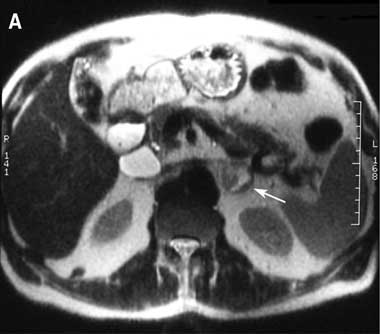

In general, imaging studies are justified only after the diagnosis of phaeochromocytoma has been established biochemically. Currently available imaging methods for localisation of phaeochromocytoma can be grouped into anatomic modalities (computed tomography [CT] and magnetic resonance imaging [MRI]) and functional imaging modalities (scintigraphy). CT and MRI (Box 2A) have a sensitivity of 90%–95%, with MRI being superior for detecting extra-adrenal tumours. However, both offer poor specificity (as low as 50% in some reports).20

The most commonly used functional study for detecting phaeochromocytoma is scintigraphy with 131I-labelled metaiodobenzylguanidine (131I-MIBG), which has specificity of over 95% but sensitivity of only 77%–90%.21 Scintigraphy using MIBG labelled with 123I instead of 131I is reported to yield superior images, but the short half-life of this isotope (13.2 hours) limits its use to metropolitan centres with a nearby cyclotron (Box 2B).